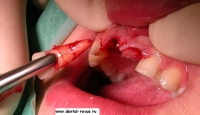

4. Рассечение круговой связки перитомом.

5. Удаление зуба.

6. Кюретаж, контроль сохранности вестибулярной стенки лунки.